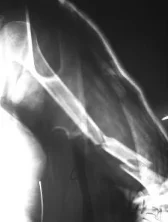

Humeral Shaft Fracture

- Possible associated injury to The Radial nerve (why?)(signs?)

Humeral Shaft Fracture- Management

- Conservative: U-shape slab) / splint / orthosis

- Gravity maintains reduction